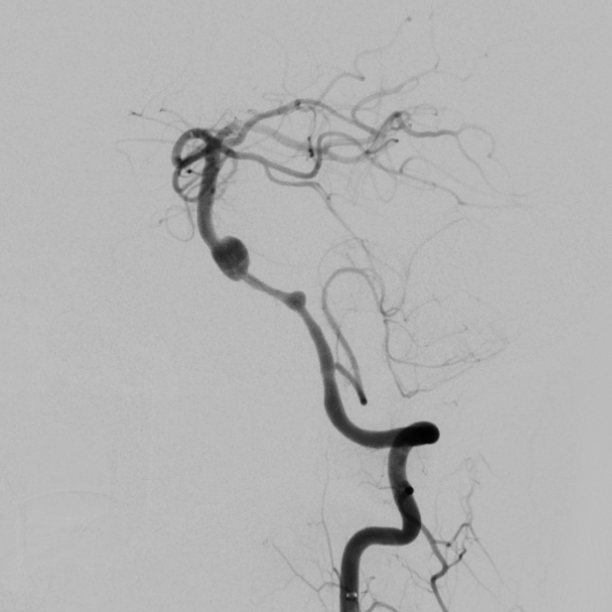

将Phenom™ 27微导管超选进入左侧大脑后动脉内,释放一枚3.25×35mm Pipeline™ Flex血流导向密网支架,远端定位在动脉瘤以远7mm,在动脉瘤处推密,近端定位在PICA起始部上端或远端,支架打开顺利。导引导管内推注替罗非班12mL,支架导管及微导管常规按摩,促进支架贴壁。

术后造影显示动脉瘤内造影剂滞留明显,载瘤动脉通畅。